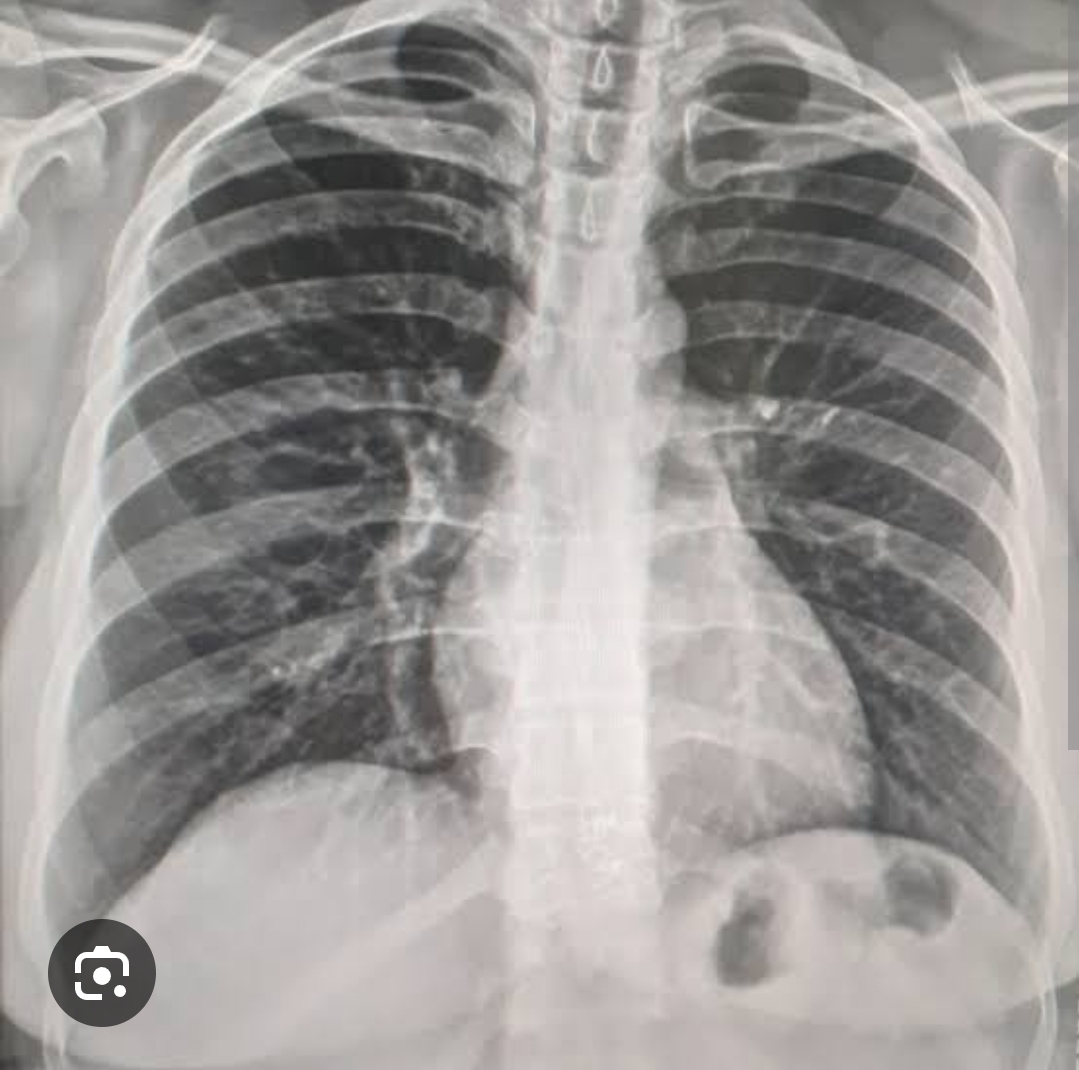

Q

Presença de líquido nos alveolos de modo que acomete todo o parenquima pulmonar.

Pulmão com consolidações difusas com aspecto de algodão e com broncograma .